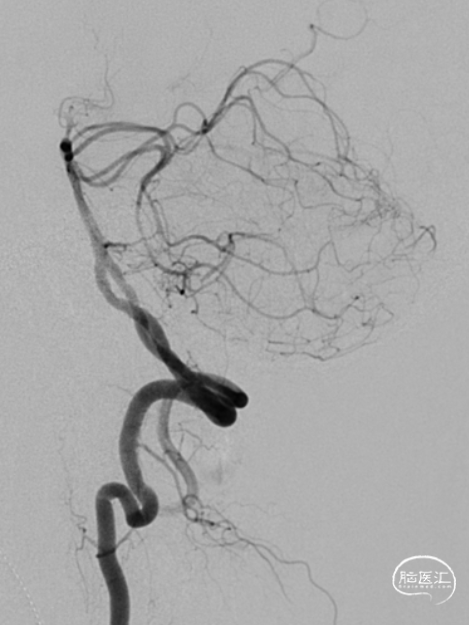

MRA:基底动脉重度狭窄

椎动脉后循环旋转造影

椎动脉V2、V3段迂曲,若不建立良好通路,则后续球囊支架无法到位释放。

基底动脉狭窄位于双侧AICA开口处,且无双侧PICA,其供血区由双侧AICA、SCA分支代偿供血。

术中如何扩张基底动脉的同时保护双侧AICA通畅是手术成功的关键。